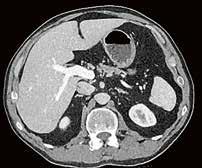

Fall 1:

Biphasische Abdomen-CT bei einer deutlich adipösen Patientin. Hier lässt sich sowohl Dosis sparen als auch die Qualität der Rekonstruktionen verbessern. Beispielsweise findet sich deutlich weniger Bildrauschen, insbesondere im Bereich der parenchymatösen

Fall 2:

Portalvenöse Abdomen-CT. Auch hier ist die Dosis am Aquilion Prime SP mit AiCE geringer, zudem auch hier geringeres Bildrauschen mit sehr guter Abgrenzbarkeit, beispielsweise von Leberläsionen.

Abb. 1 a: biphasische Abdomen-CT, Canon Aquilion Prime, Rekonstruktion: AIDR 3D; DLP 1003,6 mGy × cm / 18,1 mSv. Abb. 2 a: biphasische Abdomen-CT, Canon Aquilion Prime, Rekonstruktion: AIDR 3D; DLP 1003,6 mGy × cm / 18,1 mSv. Abb. 1 b: biphasische Abdomen-CT, Canon Aquilion Prime, Rekonstruktion: AiCE; DLP 716,5 mGy × cm / 12,9 mSv. Abb. 2 b: biphasische Abdomen-CT, Canon Aquilion Prime, Rekonstruktion: AiCE; DLP 716,5 mGy × cm / 12,9 mSv. Oberbauchorgane.